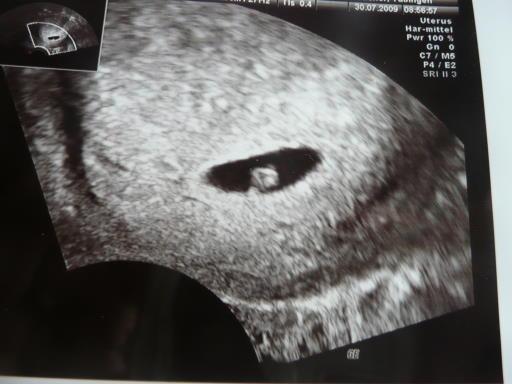

5+4 von gestern!!! lg nadine

Bild zu Hier mein erstes us-bild in - Forum für März - Mamis

Der punkt ganz am rand ist der embyo,und das große der dottersack! Der punkt pulsierte auch beim us,aber der arzt wollte sich noch nicht festlegen bezüglich herzschlag!

das pulsieren ist wahrscheinlich der Blutfluss, so hat mir das mein FA erklärt. Freu mich für Dich